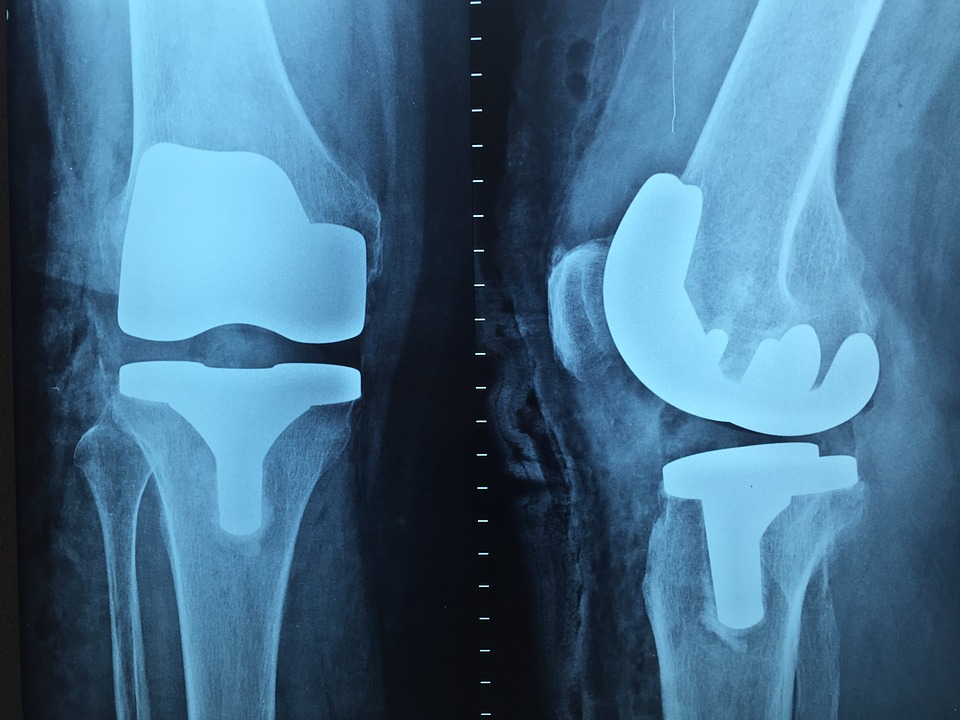

Одной из наиболее высокотехнологичных операций выполняемых в современной ортопедии является протезирование крупных суставов. В случае серьезных вывихов или переломов кость не может срастись должным образом, поэтому требуется коррекционные мероприятия.

По сложности и объему эндопротезирования выделяют несколько основных видов:

- Эндопротезирование части сустава;

- Полное протезирование сустава.

Последний вид является самым радикальным и эффективным, так как заранее удается просчитать результаты лечения. Именно благодаря высокой эффективности лечения эндопротезирование и получило такую высокую популярность.

Немаловажный вклад в развитие данной отрасли современной травматологии внесли и инженерные достижения, а именно появление высокопрочных материалов: хирургической стали, титана и полимерных сплавов.

Данные материалы способны выдерживать колоссальные нагрузки, что существенно повысило срок гарантированной службы эндопротезов. На сегодняшний день известны случаи использования протезов на протяжении десятков лет.